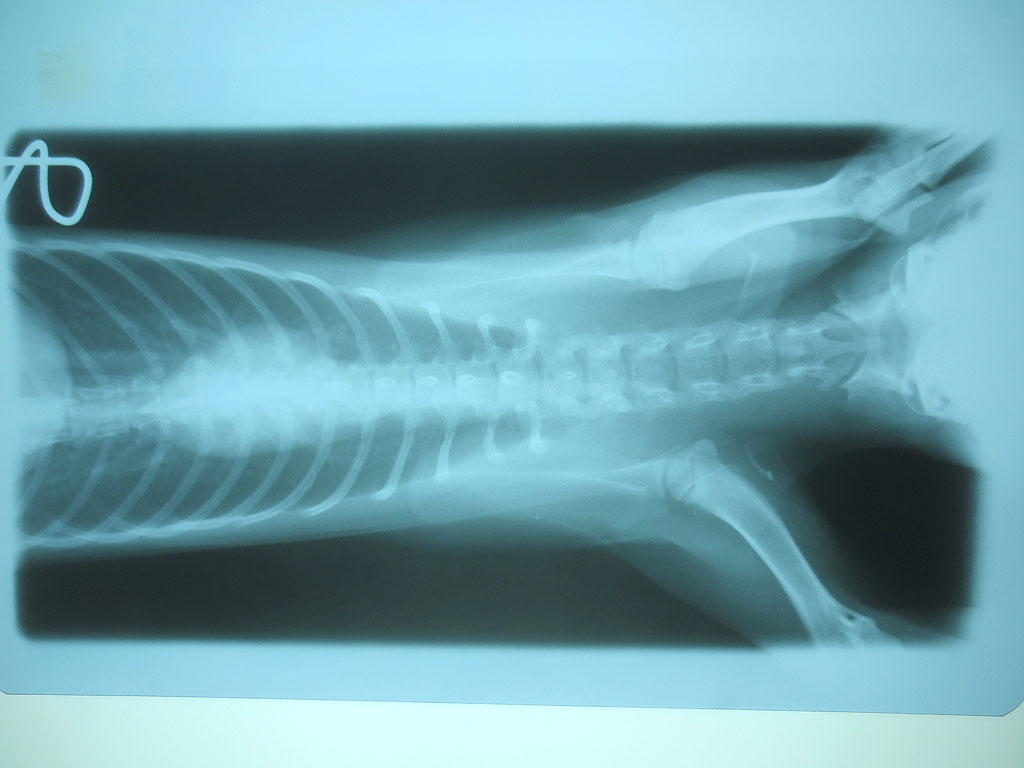

そして、レントゲンの現像も終わって、また診察室に呼ばれ、早速、レントゲンの写真を見せて頂いたのですが、いきなりですが、アビのすけの胃の中に異物が…。

紐とかだったらレントゲンに写らないそうなのですが、かなりはっきりと写っていて、何か、金属的なものを飲み込んでいるとの事…。

食パンの袋の口を結ぶ、芯に針金が入ったくるくるってひねって巻くやつの様だと先生はおっしゃったのですが、そんなものは部屋の中にはない筈なのですが、私が落としてしまったのかも知れず…。

全部で6枚、撮って頂いたのですが、後の5枚は、特に何も写っていなかったので、連続でアップさせて頂きます。